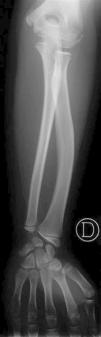

Edad ósea: 6,5 años (Greulich-Pyle). La radiografía practicada con este fin (fig. 2) muestra una imagen de características similares a la de su padre y su hermano (fig. 3).

Figura 2. Radiografía de mano y muñeca solicitada para medir la edad ósea de la paciente.

La imagen de la radiografía de la paciente (fig. 2), muestra la displasia de Madelung de la Discondrosteosis de Leri Weill. La imagen, que solamente comprende carpo y mano, muestra varios signos, aún incompletos por la corta edad de la niña, que orientan al diagnóstico:

1.Deformación de la fila proximal del carpo, en la que el hueso semilunar se ha acercado a la epífisis radial, dando al borde carpal proximal, normalmente curvo, una configuración picuda (piramidal).

2.Distancia radiocubital ampliada (apreciable aquí, entre ambas epífisis).

3.Fusión precoz de la cara ulnar de la epífisis radial.

A los pacientes con hipocrecimiento se les practica una radiografía de muñeca y mano, para medir su maduración ósea. La misma imagen es útil para investigar la posible existencia de la semiología radiológica aquí mostrada. Esto ya es posible en el escolar (aún sin deformidad visible en el antebrazo), y es un valioso instrumento diagnóstico a pesar de su sensibilidad limitada. La eventual identificación positiva debe seguirse del insalvable cariotipo y de la investigación molecular del gen SHOX en el paciente y sus familiares directos.